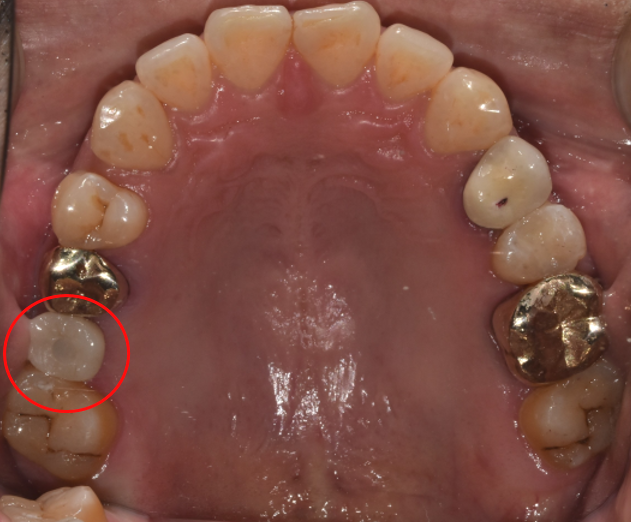

청담역치과 2021-11-01 치아 중앙에 구멍, 보이시나요?

치료 후 사진을 자세히 보시면 사진 중에서 구멍이 살짝 보이실 것입니다.

그것이 바로 위에 설명드렸던 'SCRP 타입'의 보철물인데요.

기존에 주로 사용하는 보철물은 시술하고 나서 나사가 풀리기도 하고 인공치아가 파손되면 보철물을 다 제거해야 했는데요.

이런 단점을 보완하기 위한 보철물이 바로 SCRP 타입 보철물입니다.

치료 이후에 보수해야 하는 상황이 생기면 중앙에 보이는 구멍을 통해 나사를 조일 수 있고 '쉽게 보수할 수 있다'라는 장점이 있어,

요즘 임플란트 치료 중에서 가장 선호하는 보철물이기도 합니다.

(구멍을 뚫고 그대로 방치하면 충치가 발생할 수 있으므로,

수술하고 나면 구멍을 레진으로 막고 있습니다.

이후에 보수할 경우에는 레진 부분만 제거한 후,

보수를 진행한다고 생각하시면 됩니다. )